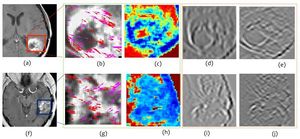

- 4.6 Texture Descriptors to distinguish Radiation Necrosis from Recurrent Brain Tumors on multi-parametric MRI